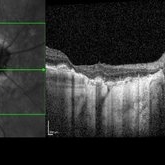

Diabetic Macular Edema

May 28 2016 by Olivia Rainey

Optical coherence tomography of an 54-year-old female with diabetic macular edema affecting both eyes. Patient has a history of proliferative diabetic retinopathy s/p PRP/PPV/MP/EL, and glaucoma s/p tube shunt in both eyes. There has been a persistence of her macular edema and limited response to antiVEGF therapy, which puts into question whether there is another cause for her edema. Leading the possible causes is her renal insufficiency and fluid retention. Patient was seeing 20/50 in the right eye and 20/80 in the left eye.

Photographer: Olivia Rainey

Imaging device: Heidelberg Spectralis

Condition/keywords: anti-VEGF, diabetic macular edema, edema, glaucoma, optical coherence tomography (OCT), pan-retinal photocoagulation (PRP), proliferative diabetic retinopathy (PDR)